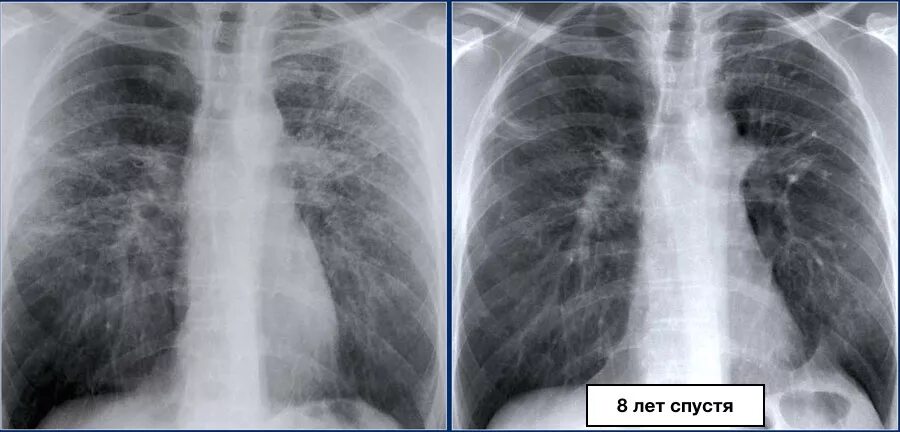

Как выглядит фиброз легких